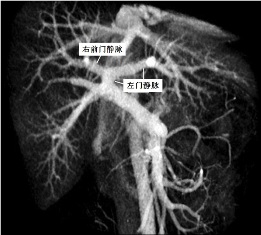

当时清晰地像下面这张图显示门静脉还不是一件容易的事。 MRI 门静脉和肝静脉显影

而Rosch在上述试验中并没有停止于仅仅创造出另一种门静脉造影技术。在开始探索在动物体内行经颈内静脉门脉造影,作为显示门脉循环的一项新技术时候,受Charles Dotter 的信念的影响,他们相信任何诊断性导管术都应被视为一种潜在的治疗工具及一种手术刀的替代工具,所以发明肝内肝静脉和门静脉大分支间的通道作为门腔分流途径在后来几乎是顺理成章和水到渠成的事。 |